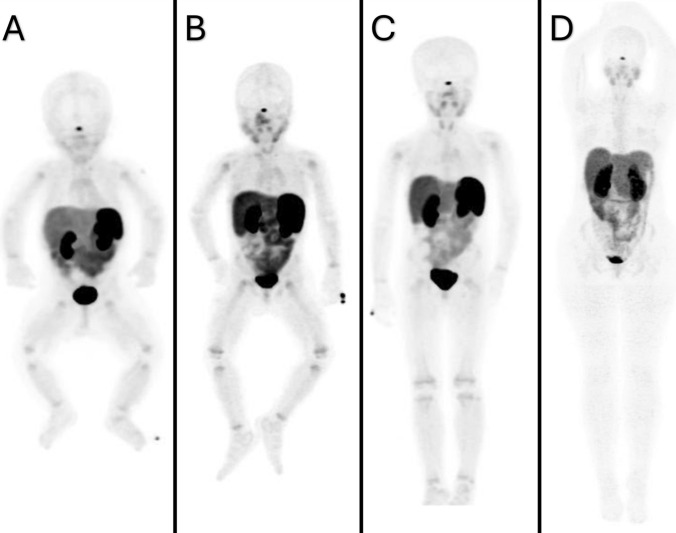

Somatostatin receptors (SSTRs) are G protein-coupled transmembrane receptors that serve as a specific molecular target for a number of radiopharmaceuticals utilized for the imaging of neuroendocrine tumors (NETs). 68Ga-DOTA-TATE is a somatostatin analog that demonstrates a high affinity for SSTR2. Pediatric malignancies, such as neuroblastoma, pheochromocytoma, and paraganglioma, have been shown to express SSTR2, and 68Ga-DOTA-TATE is currently being used to evaluate these pediatric neoplasms. We aimed to analyze the distribution pattern of 68Ga-DOTA-TATE based on age and location in pediatric patients.

We retrospectively analyzed 247 consecutive 68Ga-DOTA-TATE whole-body PET/CT scans performed in our department from May 2015 to April 2024 in pediatric patients with known or suspected neuroblastoma, neuroendocrine malignancy, pheochromocytoma, and paraganglioma. 93 subjects were included in this study who were disease-free at the time of imaging and had no tracer-avid lesion on 68Ga-DOTA-TATE PET/CT. The patients were divided into four groups according to age: infant (0–2 years), pre-school (3–6 years), school (7–12 years), and adolescent (13–18 years). A comparison of the SUV values of each organ across age groups was performed.

The highest levels of physiological uptake were observed in the spleen across all age groups, except for infants, who demonstrated the highest SUV values in the kidneys. 68Ga-DOTA-TATE uptake in the parotid glands, submandibular glands, thyroid gland, thymus, liver, spleen, adrenal glands, stomach, intestines, uterus, prostate, and testes demonstrated a statistically significant increase in the adolescent age group. In contrast to all internal organs, the lowest SUV max values were observed for all growth plates within the adolescent age group.

This study presents the bio-distribution pattern of 68Ga-DOTA-TATE in pediatric patients, according to age and location. The ranges of the SUVmax and SUVmean values of 68Ga-DOTA-TATE obtained in the various organs are of paramount importance for accurately diagnosing malignancy in 68Ga-DOTA-TATE PET/CT studies.